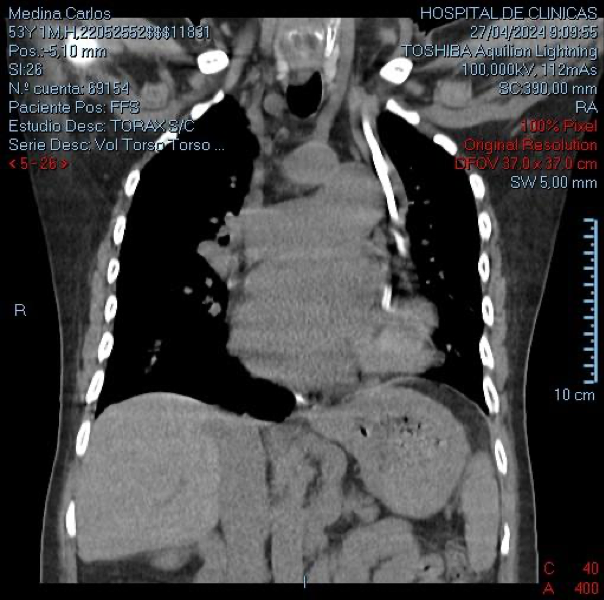

Presentamos un paciente con hiperamoniemia, que durante el estudio de la causa se diagnosticó agenesia de la vena porta, con anastomosis de la vena mesentérica a la vena renal izquierda. Ante el cuadro clínico y humoral, con compromiso neurológico, se decidió la colocación de un catéter doble lumen y se inició tratamiento mediante hemodiálisis convencional. Se colocó catéter por vía yugular izquierda presentando ubicación atípica y con mala cinética por lo que debió colocarse otro catéter doble lumen en vena subclavia derecha, ubicándose en posición convencional. La radiografía de control muestra la ubicación de ambos catéteres colocados.

Además de la anomalía vascular de la vena porta y de las cavidades cardíacas que presentes en este paciente, se detectó una anomalía vascular en las venas centrales. Se debe tener presente la posibilidad de que exista esta asociación de variantes anatómicas cuando debemos abordar vías centrales, en nuestro caso con catéter de doble lumen para tratamiento dialítico. El tip del catéter izquierdo se ubicó a nivel de seno coronario, donde el flujo sanguíneo resultó deficiente para efectuar el tratamiento dialítico. Se adjunta gráfico con esquema de las alteraciones más frecuentes de la vena cava superior doble.(1)

La TAC mostró una vena cava superior izquierda y otra derecha